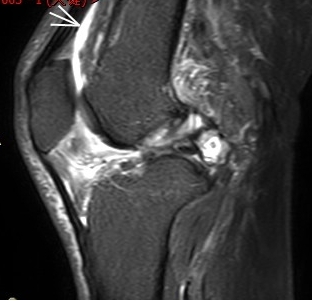

1. “咯吱響”+“卡頓感”——半月板的“碎玻璃警報(bào)”

場景:下蹲時(shí)膝蓋“咯噔”彈響,起身像被“卡住”

MRI偵查:精準(zhǔn)捕捉半月板撕裂或變性(半月板內(nèi)高信號),避免拖成“關(guān)節(jié)交鎖”

(半月板撕裂)